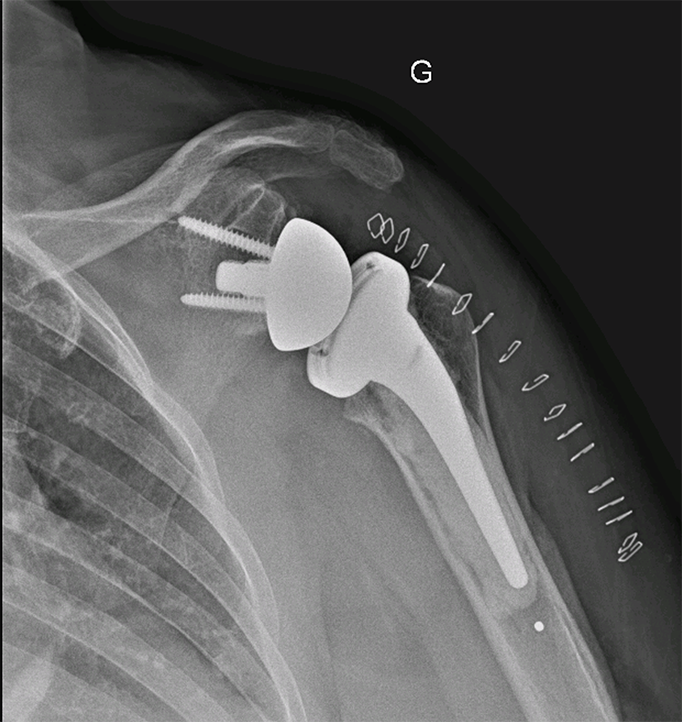

L’intervention se fait par une voie d’abord se situant à l’avant de l’épaule. L’abord de l’articulation nécessite une section du tendon du sous-scapulaire, qui sera réparé en fin d’intervention. Le chirurgien sectionne la tête humérale pour préparer l’os à l’aide de râpe et de compacteur pour positionner la tige humérale. Il prépare ensuite la glène de l’omoplate pour y implanter l’autre versant prothétique qui sera fixé dans l’os avec des vis et un plot recouvert d’un revêtement permettant une bonne tenue osseuse. Le chirurgien dispose de plusieurs tailles pour les implants qui sont adaptés à la morphologie de chaque patient. En fin d’intervention, le chirurgien positionnera un drain ou redon qui limitera la survenue d’un hématome post opératoire et qui sera retiré à 48 heures.

Prothèse épaule inversée - Dr Dumoulin